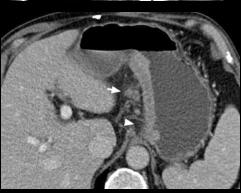

La Ct scanner est examen de cle

pour diagnostic locoregionale et metastatique de

tumeur de l'estomac .Soit elle verifie la taille ,

l'epaissisement

de la parietale , la circonference du tumeur ,sa bord et

l'extention du tumeur au structure voisinage

, ganglionaire et lesions metastatiques au autres organes :

peritoine , hepatique ou pulmonaire . La technique realise en pratiquee apres remplisage de

l'estomac avec eau ou produit de contrast iode diluee (

700ml , 15 minute avant et 250ml au temp de realise

Cancer de l'estoma type

2 bourgeon ulceree a region antrale extention

locale et ganglionaire |

|

Adeno carcinoma de l'estoma de la

petit coubure , extention locale et ganglionaire